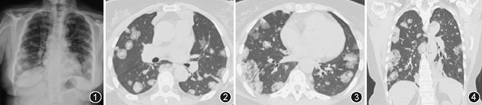

患者女,62岁,主因"间断咳嗽、咳痰2个月余"于2017年9月27日就诊。患者2个月来间断咳嗽,每日咳痰数口,无发热、咯血、胸痛、呼吸困难等症状。1个月前于外院X线胸片显示双肺多发结节影,首先考虑特殊感染,不除外肿瘤(图1)。遂来我院门诊就诊。患者自发病以来饮食可,二便如常,体重无明显下降。既往体健,无吸烟饮酒史。无放射线及毒物接触史。体格检查:体温36.3 ℃,脉率88次/min,呼吸频率24次/min,血压140/60 mmHg(1 mmHg=0.133 kPa)。指尖脉氧饱和度93%,双肺散在少许湿啰音。心律齐,无杂音。腹平软,无压痛。双下肢不肿。

初步诊断为肺部多发结节原因待查。于我院门诊查血常规白细胞为5.15×109/L,中性粒细胞为0.52,嗜酸粒细胞百分比为0.09,C反应蛋白(CRP)为2 mg/L。1-3-β-D葡聚糖(G试验)、血清半乳甘露聚糖试验(GM试验)、隐球菌荚膜抗原阴性;抗核抗体(ANA)阳性(颗粒型1∶320,胞质型1∶320,均质型1∶320),抗ds-DNA(IIF法)阴性,抗dsDNA(ELISA法)为202 IU/ml(正常参考值:<100 IU/ml),抗中性粒细胞胞质抗体(ANCA)阴性。总IgE为73 kU/L(<100 kU/L)。肿瘤标志物细胞角蛋白19片段为5.7 μg/L(正常参考值:<3.3 μg/L),组织多肽抗原为150.1 U/L(正常参考值:<120 U/L),胃泌素释放前体为91.9 ng/L (正常参考值:<69.2 ng/L)。肺功能通气功能正常,支气管舒张试验阳性,FEV1改善率为12.6%(290 ml)。胸部高分辨率CT(HRCT)显示双肺多发大小不等、形态不规则团块实变灶(图2,图3,图4)。全身PET-CT显示双肺多发磨玻璃及软组织密度实变灶,葡萄糖代谢轻度增高(图5)。肛周葡萄糖代谢增高灶,考虑痔疮可能大。脑部、骨骼、肝脏等其余脏器未见葡萄糖代谢异常灶。

IMA分化好、发展慢,故临床症状出现较晚,主要表现为咳嗽、咳痰,部分患者每日咳痰量>100 ml,晚期患者可出现呼吸困难[2]。影像学表现为结节影或肺炎样改变。典型的结节型黏液腺癌CT表现为实性或部分实性结节,少见纯磨玻璃结节[3]。与其他类型肺癌相比,更容出现空泡征或假空洞征,占IMA的40%~78%。其病理学基础是肿瘤细胞沿管壁浸润性生长,使管腔形成活瓣样阻塞,气体容易进入肺泡腔但难以出去,导致肺泡腔过度充气,表现为小空泡征或假空洞。而被肿瘤细胞分泌的黏液填充的肺泡腔,则表现出来低于肌肉组织的实性密度影[4],随时间推移,黏液中水分被重吸收而蛋白成分增加,CT值会逐渐上升。结节周围若存在磨玻璃影往往边界不清,病理上磨玻璃影相当于分泌到肺泡间隙的黏液、聚集的巨噬细胞或被肿瘤细胞部分替代但未被完全填充的肺泡间隙。